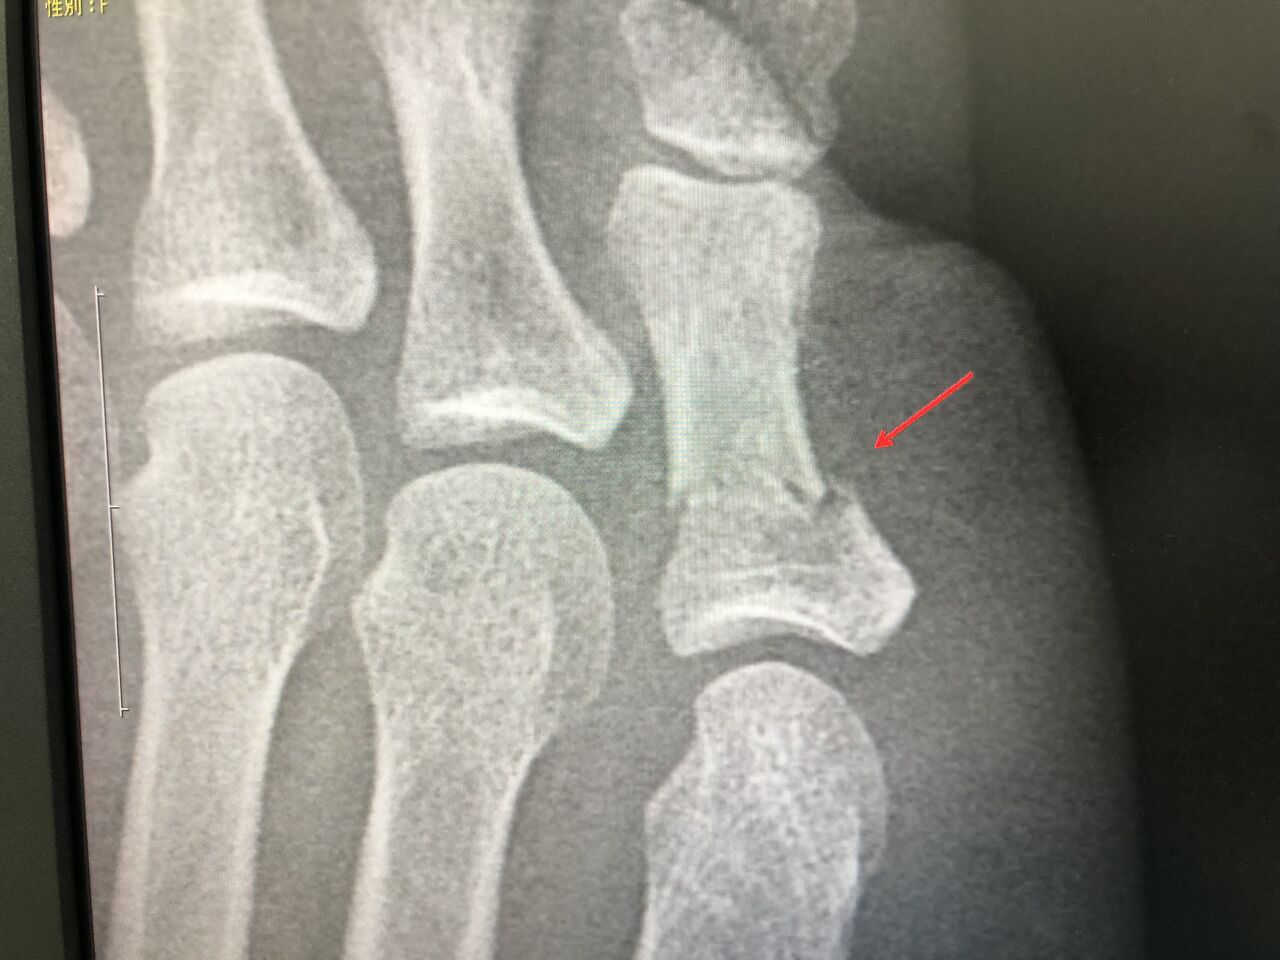

超音波骨治療器(LIPUS)で早期復帰へ

転位骨折が 3週間で骨融合